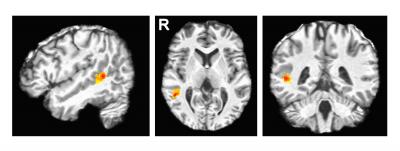

It's on the right side of the brain behind the ear, in a region called the posterior superior temporal sulcus (pSTS).

In a paper published today in the Journal of Neuroscience , the researchers report that they used functional magnetic resonance imaging (fMRI) to identify a region of pSTS as the part of the brain activated when test subjects looked at images of people making different facial expressions.

fMRI detects increased blood flow in the brain, so the research group was able to obtain images of the part of the brain that was activated when the students recognized different expressions. Regardless of the expression they were looking at, all the students showed increased activity in the same region--the pSTS.